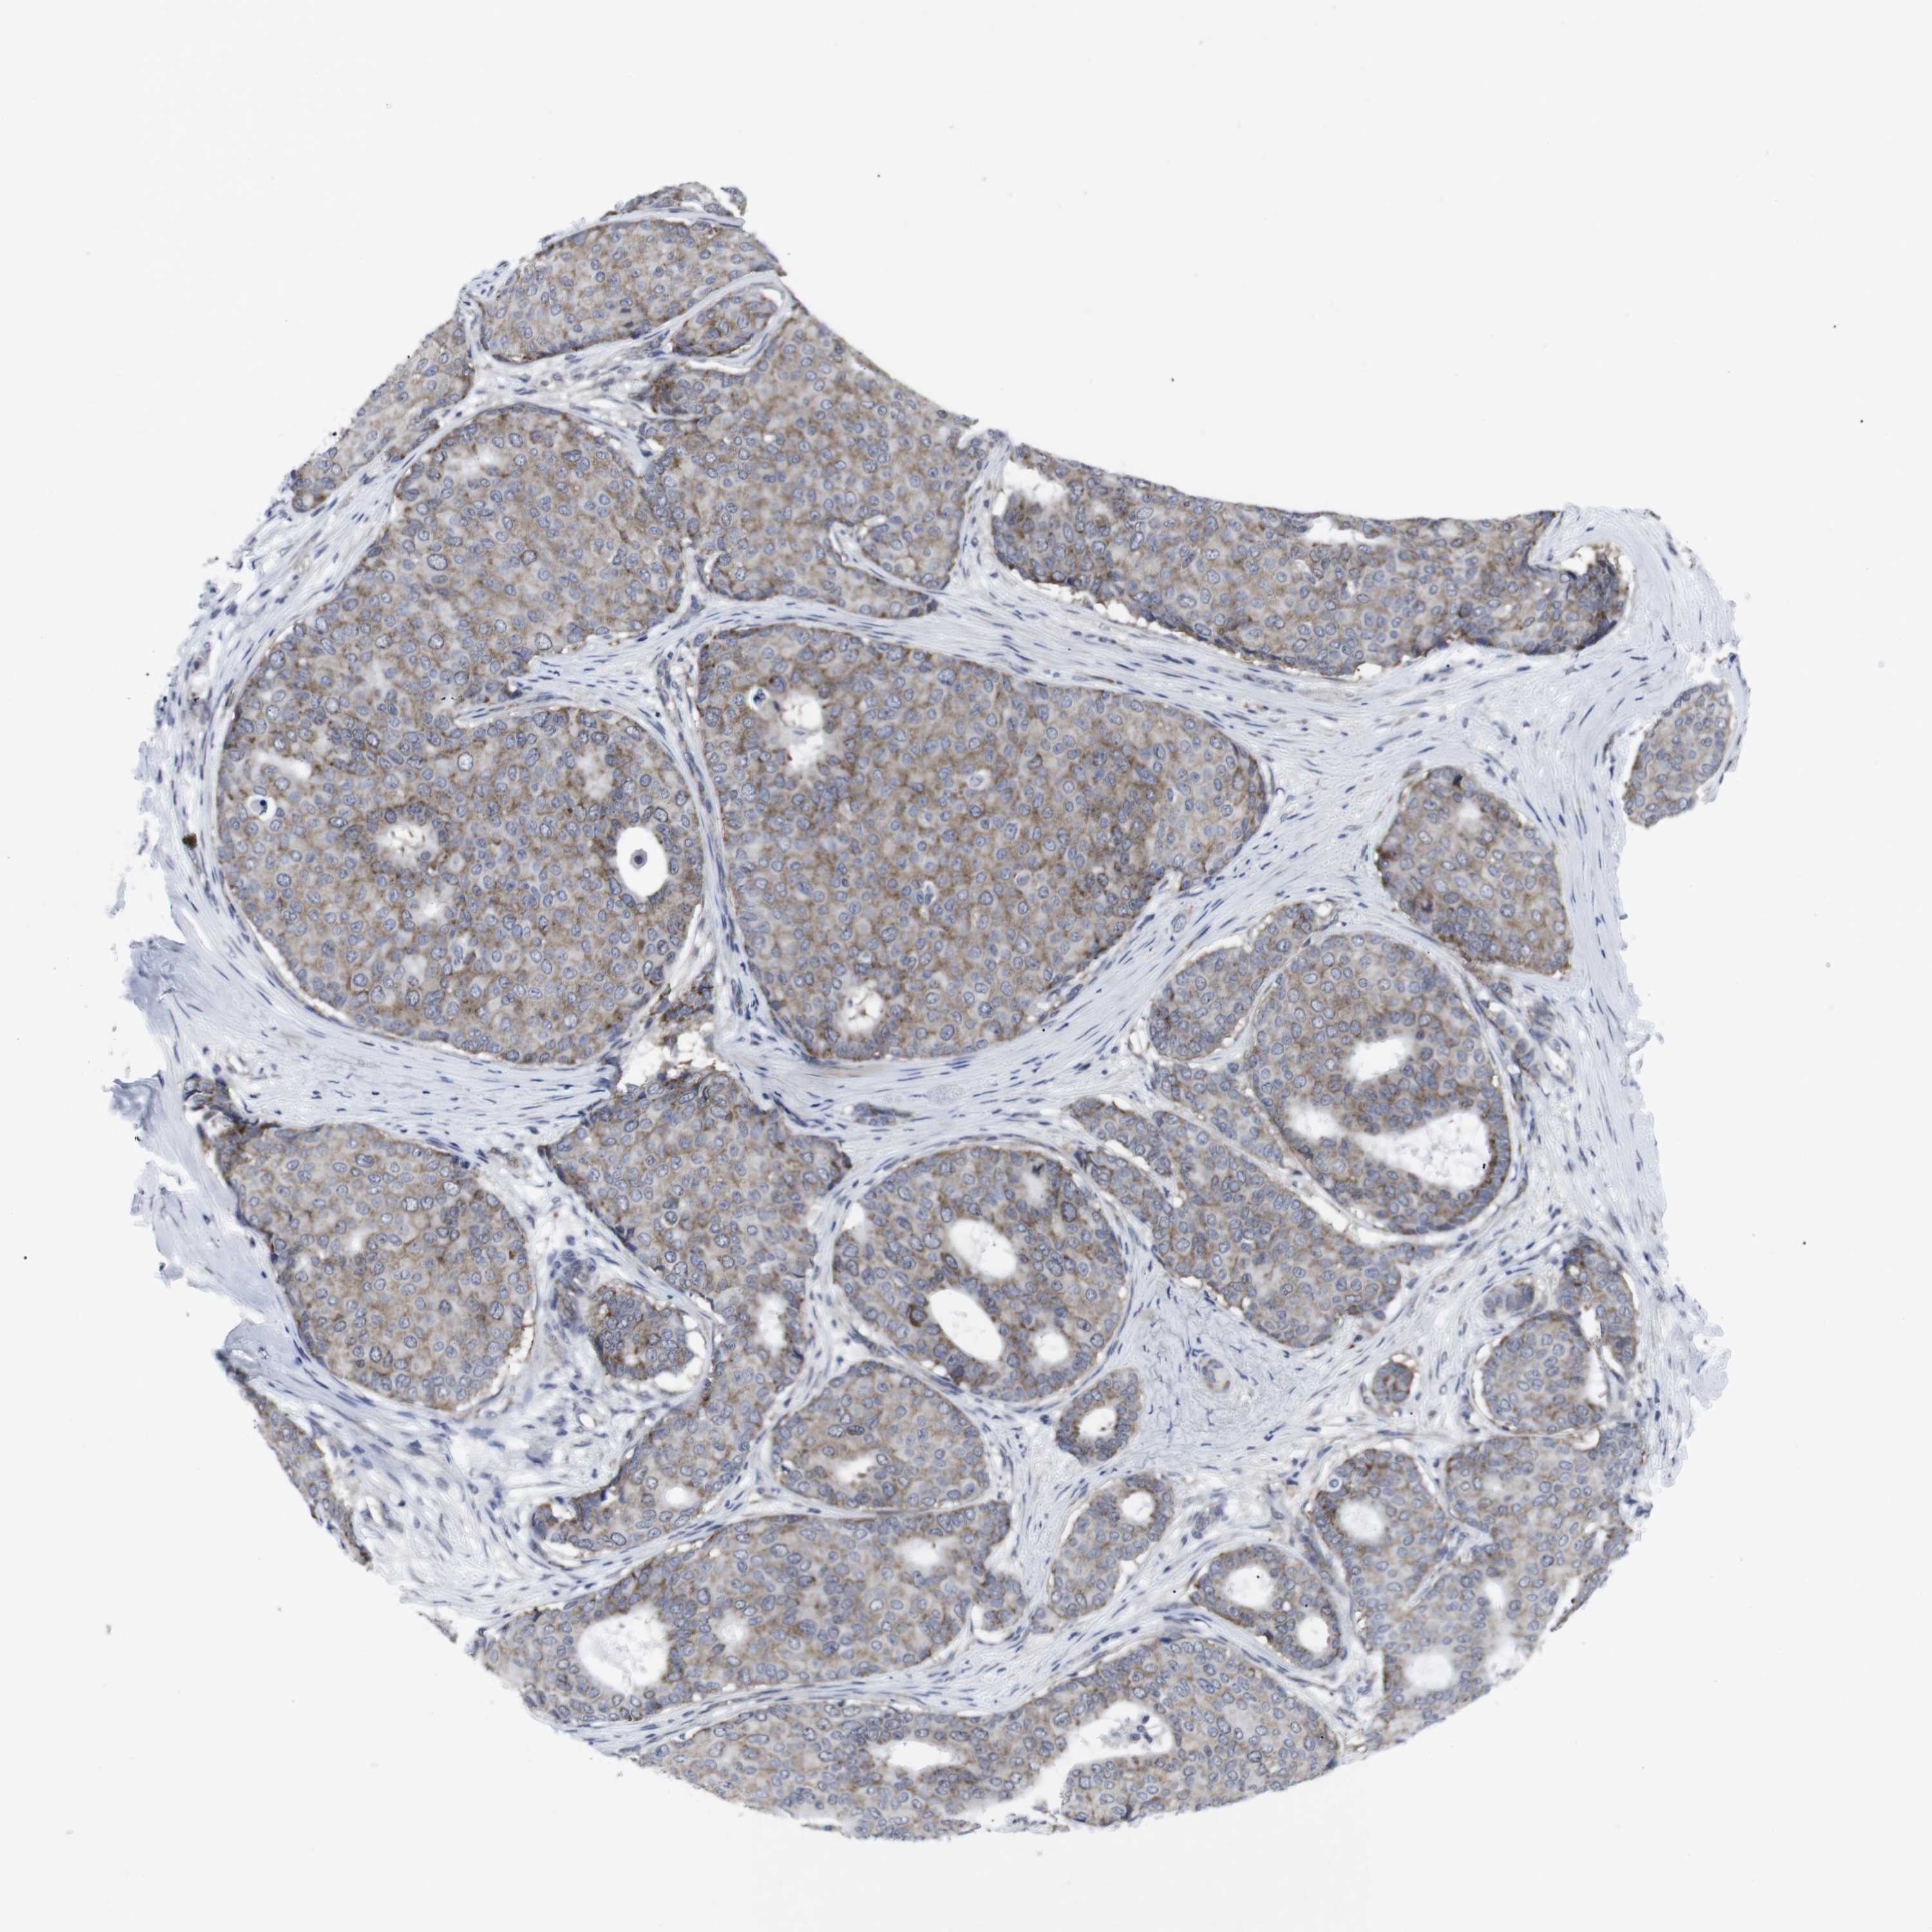

CANCER BREAST CANCER Show tissue menu

BRCA TCGA BRCA VALIDATION PROTEIN EXPRESSION

ANTIBODIES

AND

VALIDATION